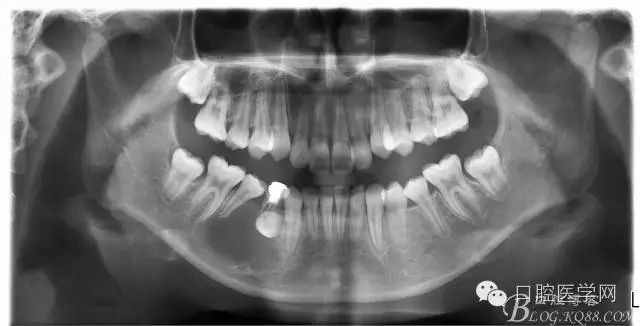

查:右側(cè)第二前磨牙第一乳磨牙恒尖牙頰側(cè)前庭溝隆起,捫有乒乓球感。曲斷及CT示:右側(cè)第二前磨牙第一乳磨牙恒尖牙根尖區(qū)有一囊腫,頰舌側(cè)骨板極薄,牙根無吸收,第二前磨牙牙根位于囊腫中,第一雙尖牙牙冠遠(yuǎn)中水平向阻生,牙冠位于囊腫中。經(jīng)協(xié)議:手術(shù)摘除創(chuàng)傷大,同意開創(chuàng)引流保守治療。

否認(rèn)手術(shù)禁忌癥及過敏史。消毒,局麻下鋪巾,拔出第一乳磨牙,有囊液溢出,擴(kuò)大開放引流孔,取部分囊壁送病理,生理鹽水沖洗,置引流管縫合固定。病理報(bào)告:囊腫。八月后局麻拔除第一雙尖牙刮凈剩余變小的囊壁。

術(shù)后一個(gè)月 三個(gè)月 五個(gè)月 八個(gè)月 拔除第一雙尖牙后 曲斷片: